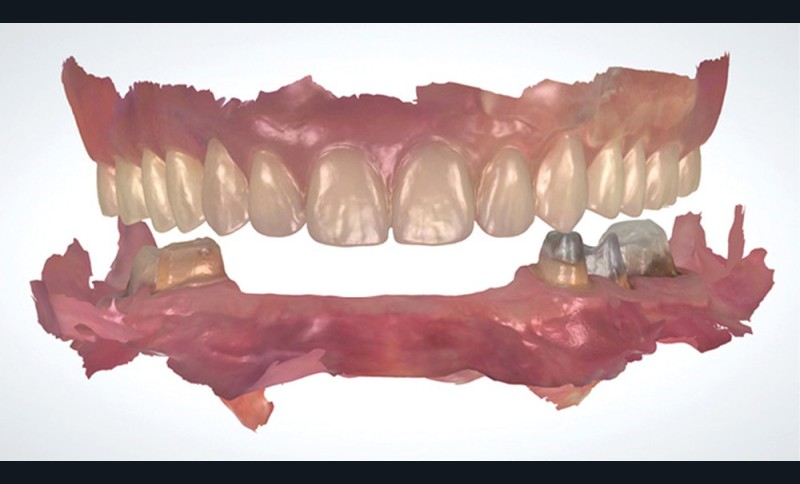

L’empreinte optique permet de positionner des points dans l’espace et l’ensemble de ses points crée le fichier 3D de l’empreinte. Ce référencement offre la possibilité d’enregistrer les arcades sans mordus ou cire d’occlusion dans les cas où le calage postérieur est absent (fig. 1).

La corrélation de fichiers est un vrai facilitateur pour les plans de traitement prothétique ; que ce soit pour le suivi des cas, ou dans des cas particuliers comme celui de la couronne sous châssis. Cette situation est toujours préjudiciable pour le patient en empreinte conventionnelle, car elle oblige à priver ce dernier de sa prothèse adjointe le temps que le laboratoire conçoive la couronne. Avec l’empreinte optique, il suffit d’enregistrer le crochet et sa position par rapport à la préparation pour que le prothésiste puisse concevoir une prothèse adaptée à la cavité buccale et à la prothèse amovible. Autre cas particulier, lors de la réalisation d’inlay-core, les logiciels de laboratoire ont des algorithmes qui autorisent la conception en seul temps de l’inlay-core et de la couronne avec un calcul des morphologies des éléments pour qu’ils respectent à la fois l’homothétie et les épaisseurs minimales de matériau (fig. 3 et 4).